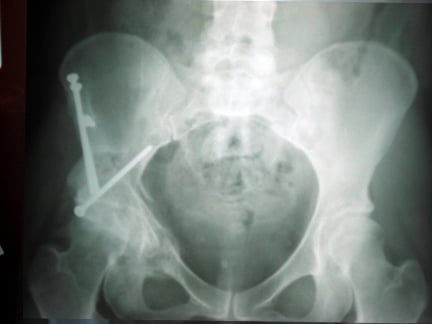

The image below is an x-ray of a patient’s hip 1 year after femoral osteotomy and shows the permanent screws and metal plate used to position the bone.

Femoral osteotomy

This type of hip osteotomy surgery focuses on correcting the hip joint ball at the top of the thigh bone called the femur.

- The top of the femur is cut to release the ball of the hip joint

- The ball is repositioned with temporary screws

- X-rays are used to help the surgeon decide if the new placement is correct

- When they are happy with the alignment, they secure it into the new position with a metal plate and screws